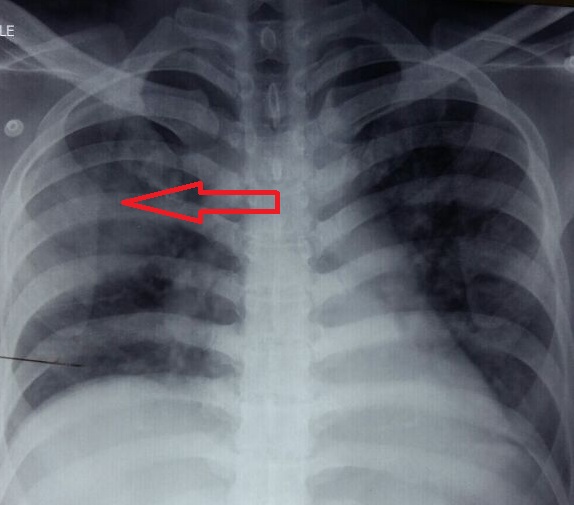

Stenotrophomonas maltophilia: an unusual pathogen for pneumonia in an immunocompetent patient

Stenotrophomonas maltophila, pneumonia, carbapenemsAbstract